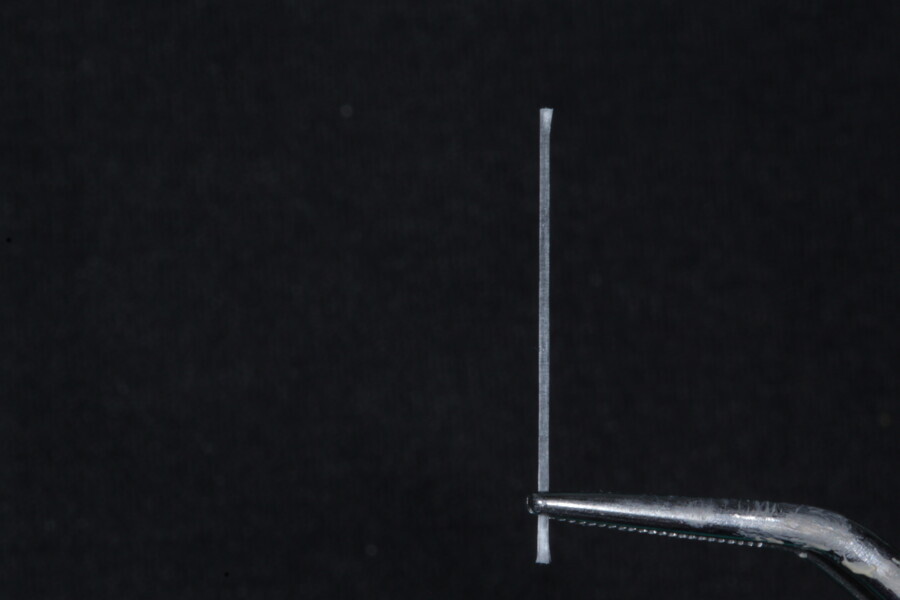

The second step focuses on reinforcing the restoration through careful fibre and FRC selection and placement. Tooth preparation should involve minimal removal of tooth structure to preserve as much natural tooth as possible in preparing the cavity for the restoration. Fibres or layers of FRC (flowable, paste, cube, etc.) are then strategically placed within the prepared tooth and composite material to reinforce areas susceptible to high stress and occlusal forces based on occlusal contact mapping. This strategic selection and placement of fibres and layers of FRC is crucial for enhancing the strength and longevity of the restoration.

1. functional and aesthetic reconstruction of a maxillary anterior tooth using fibre-reinforced flexible micro-posts after endodontic treatment (Figs. 3–20);

Example 1—showing functional and aesthetic reconstruction of a maxillary anterior tooth using fibre-reinforced flexible micro-posts after endodontic treatment.